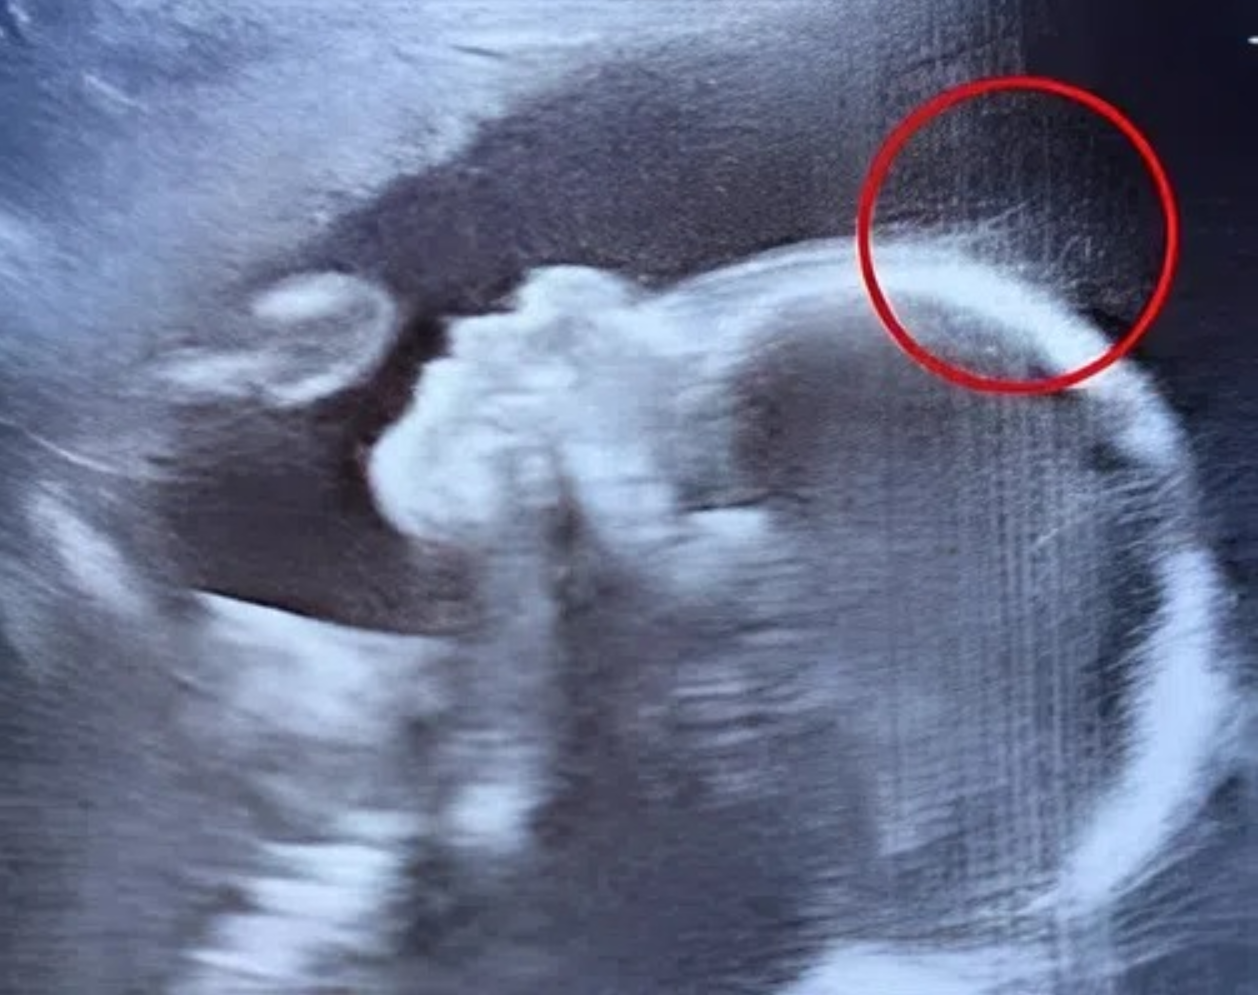

When Emily Foster walked into her 20-week pregnancy scan at the hospital, she expected a routine checkup. But what unfolded on the screen left everyone in awe. The technician’s eyes widened as she exclaimed, “Wait a second… is that hair?” Emily blinked in disbelief, and the doctor chimed in with a half-joking remark: “Looks like…

Screenshot_75